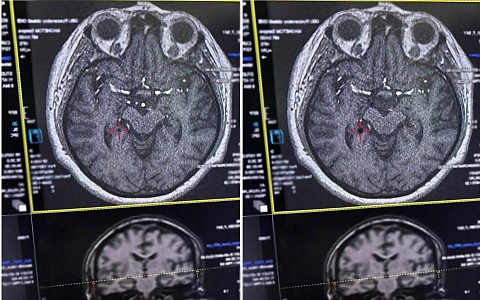

Врачи рязанской ОКБ выявили рак на ранней стадии у пациента без жалоб

Бессимптомный инфаркт выявили у мужчины в Рязани